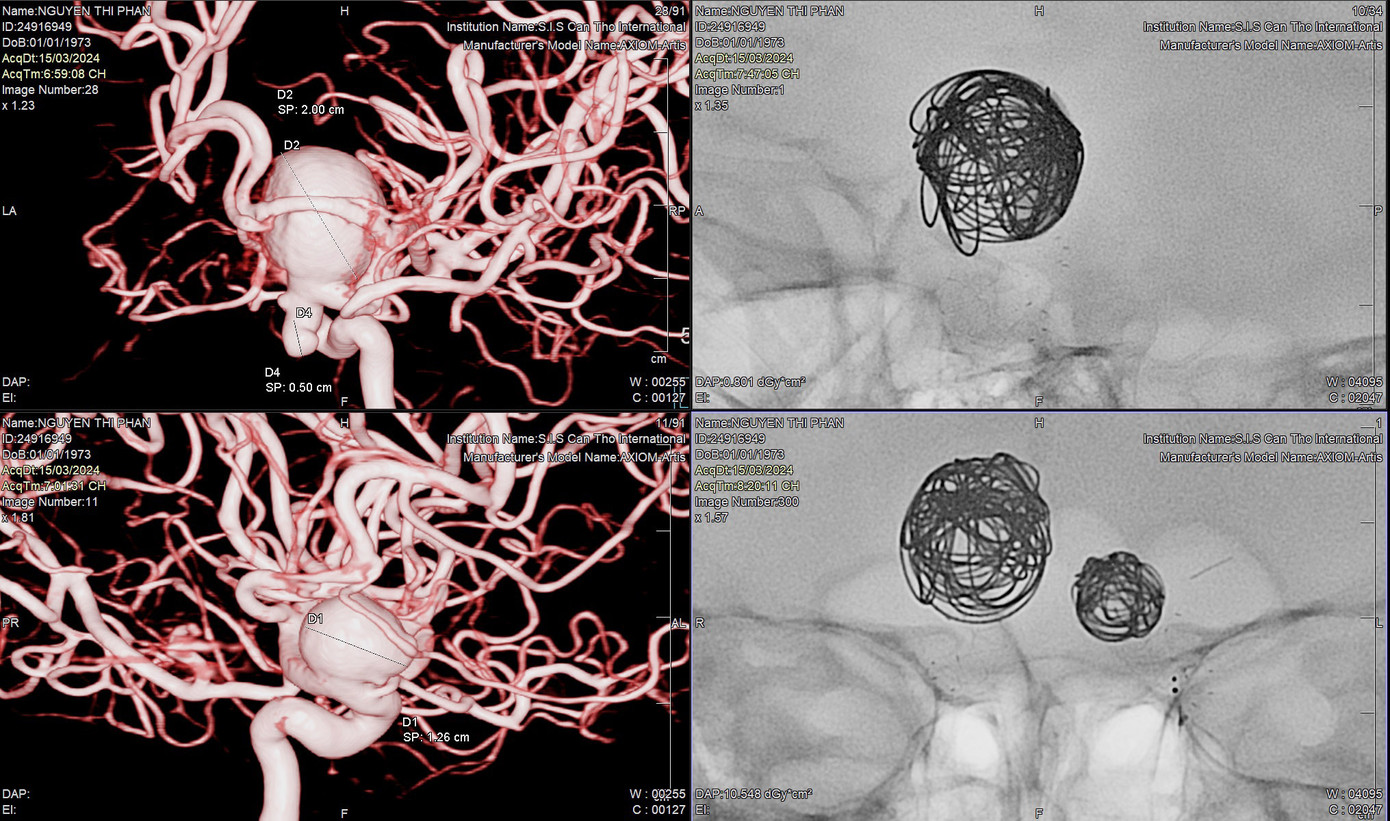

| Bệnh nhân có 3 túi phình khổng lồ dọa vỡ đã được các bác sĩ can thiệp thành công (ảnh: BVCC) |

Sau khi tiếp nhận bệnh nhân, Bệnh viện S.I.S tiến hành kiểm tra lại. Trên các hình ảnh chiếu chụp, các bác sĩ phát hiện thêm túi phình thứ 3 trong mạch máu não của người bệnh. Các túi phình có kích thước lần lượt là 20mm, 12mm và 5mm. Theo TS.BS Trần Chí Cường, đây là một trường hợp rất khó, nguy cơ tử vong cao vì việc can thiệp trên bệnh nhân có cùng lúc nhiều túi phình rất dễ bị vỡ.

Tối 15/3, sau 2 giờ can thiệp, các bác sĩ đã đặt thành công 2 stent, khóa ngòi được cả “3 quả bom nổ chậm” trong đầu người bệnh. Sau khi can thiệp, sức khỏe bệnh nhân đã ổn định và đang được tiếp tục theo dõi, điều trị tại bệnh viện.